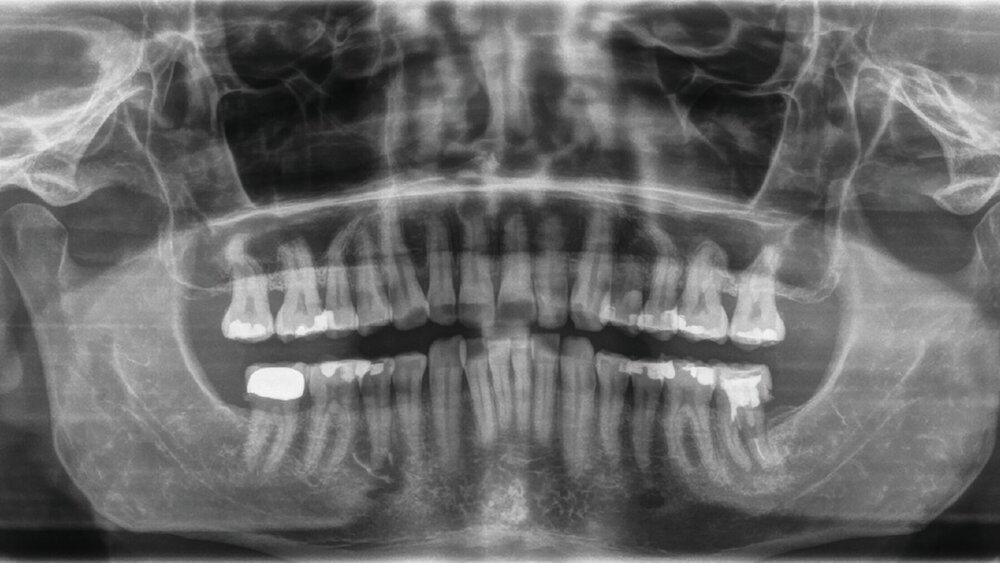

Im August 2024 stellte sich ein 50-jähriger Patient – überwiesen durch den Hauszahnarzt mit der Verdachtsdiagnose eines Sublingualabszesses – in der Notfallambulanz der Mund-, Kiefer- und Gesichtschirurgie der Universitätsmedizin Mainz vor. Anamnestisch berichtete er von erstmalig im Februar 2024 aufgetretenen Beschwerden im rechten Unterkiefer, weshalb der Zahn 45 mittels Wurzelkanalbehandlung therapiert worden sei (Abbildung 1). Die endodontische Therapie konnte laut Hauszahnarzt allerdings nie abgeschlossen werden, da der Kanal nicht vollständig trockengelegt werden konnte. Im Juli sei es dann zu einer Exazerbation der Beschwerden gekommen, einhergehend mit einer ausgeprägten Schwellung der Wange.

Nach antibiotischer Behandlung durch die orale Gabe von Clindamycin – aufgrund einer vermuteten Penicillinallergie – konnte vier Tage später der Zahn 45 extrahiert werden. Die Symptomatik persistierte jedoch und zeigte auch nach intraoraler Inzision und mehrfachem Streifenwechsel sowie Trepanation des Zahnes 46 keine Besserung (Abbildung 2). Die weitere Anamnese des Patienten war unauffällig.